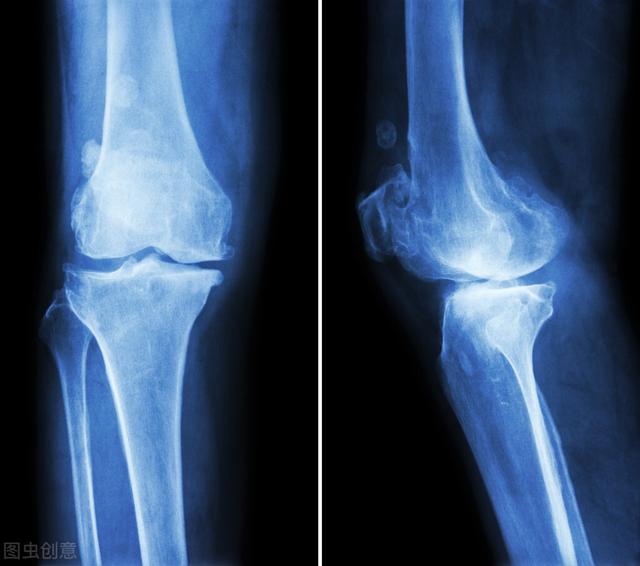

以前有患者问我,骨质疏松是不是因为钙少,而骨质增生是不是因为钙多,通过调整钙的摄入是不是能预防骨质疏松和骨质增生呢?实际上,骨质增生和骨质疏松都不是简单的钙多和钙少所导致的,骨质疏松准确讲是骨重建的过程出现了障碍,和食物钙缺乏、钙吸收障碍、内分泌异常等多种原因有关系,骨质增生则是机体在软骨损伤、关节平衡破坏后的一种代偿性反应,和人们猜测的钙多才长出骨刺大相径庭。

不过,骨质疏松却是骨关节炎的危险因素,一方面骨质疏松症患者更容易患骨关节炎,另一方面缺钙反而会促进骨质增生的发生。

骨质疏松者易患骨关节炎——骨质疏松症患者,骨骼的微观结构会发生变化,骨骼的强度下降、脆性增加,在负重的情况下,关节中软骨下骨的负重能力下降,承受的负荷减少,就会增加在骨与骨之间起缓冲保护作用的关节软骨的压力,导致关节之间摩擦加重,软骨就更容易发生破坏,骨关节炎发生的几率增大。长期缺钙可促进骨质增生——饮食中如果长期缺钙,血钙的浓度过低,就会使甲状旁腺素分泌增多,使骨钙溶出,流到血液中,当血液中钙浓度升高时,又会使降钙素的分泌增加,促进血钙向关节沉积,形成骨质增生。虽然骨质疏松与多种原因有关系,但确保食物中钙充足仍然是防治骨质疏松的基本措施。骨质疏松和骨关节炎都高发于中老年人群,中老年人因为老化的原因,本就存在骨量丢失和软骨损伤的情况,长期缺乏钙等营养元素就很可能导致发病。